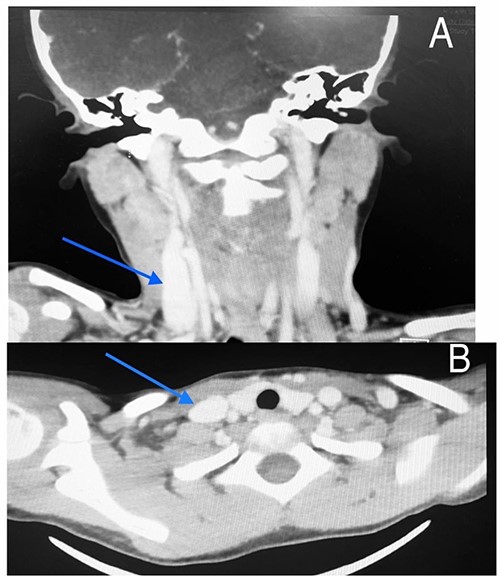

Imaging examination of the patient was done by performing CT and US. US Doppler showed a right dilated internal jugular vein (Fig. 2). The CT scan confirmed this finding, which suggested internal jugular vein phlebectasia (Fig. 3).

CT scan of the first patient in coronal view (A) and axial view (B) with blue indicate internal jugular phlebectasia.